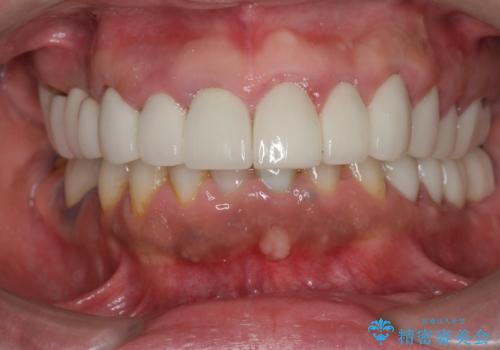

歯周外科を行い歯と歯槽骨・歯肉の関係を是正することで歯ぐきの状態を改善し、将来に亘り安定した歯周環境の維持を期待できるセラミック治療を実践します。

- 95.7万円(ジルコニアクラウン×6・仮歯×6・歯周外科)費用は治療当時の料金となります

歯ぐきが腫れたままの状態だと、違和感が生じるとともに常に炎症が存在する環境となってしまうので非常に好ましくない口腔内環境です。